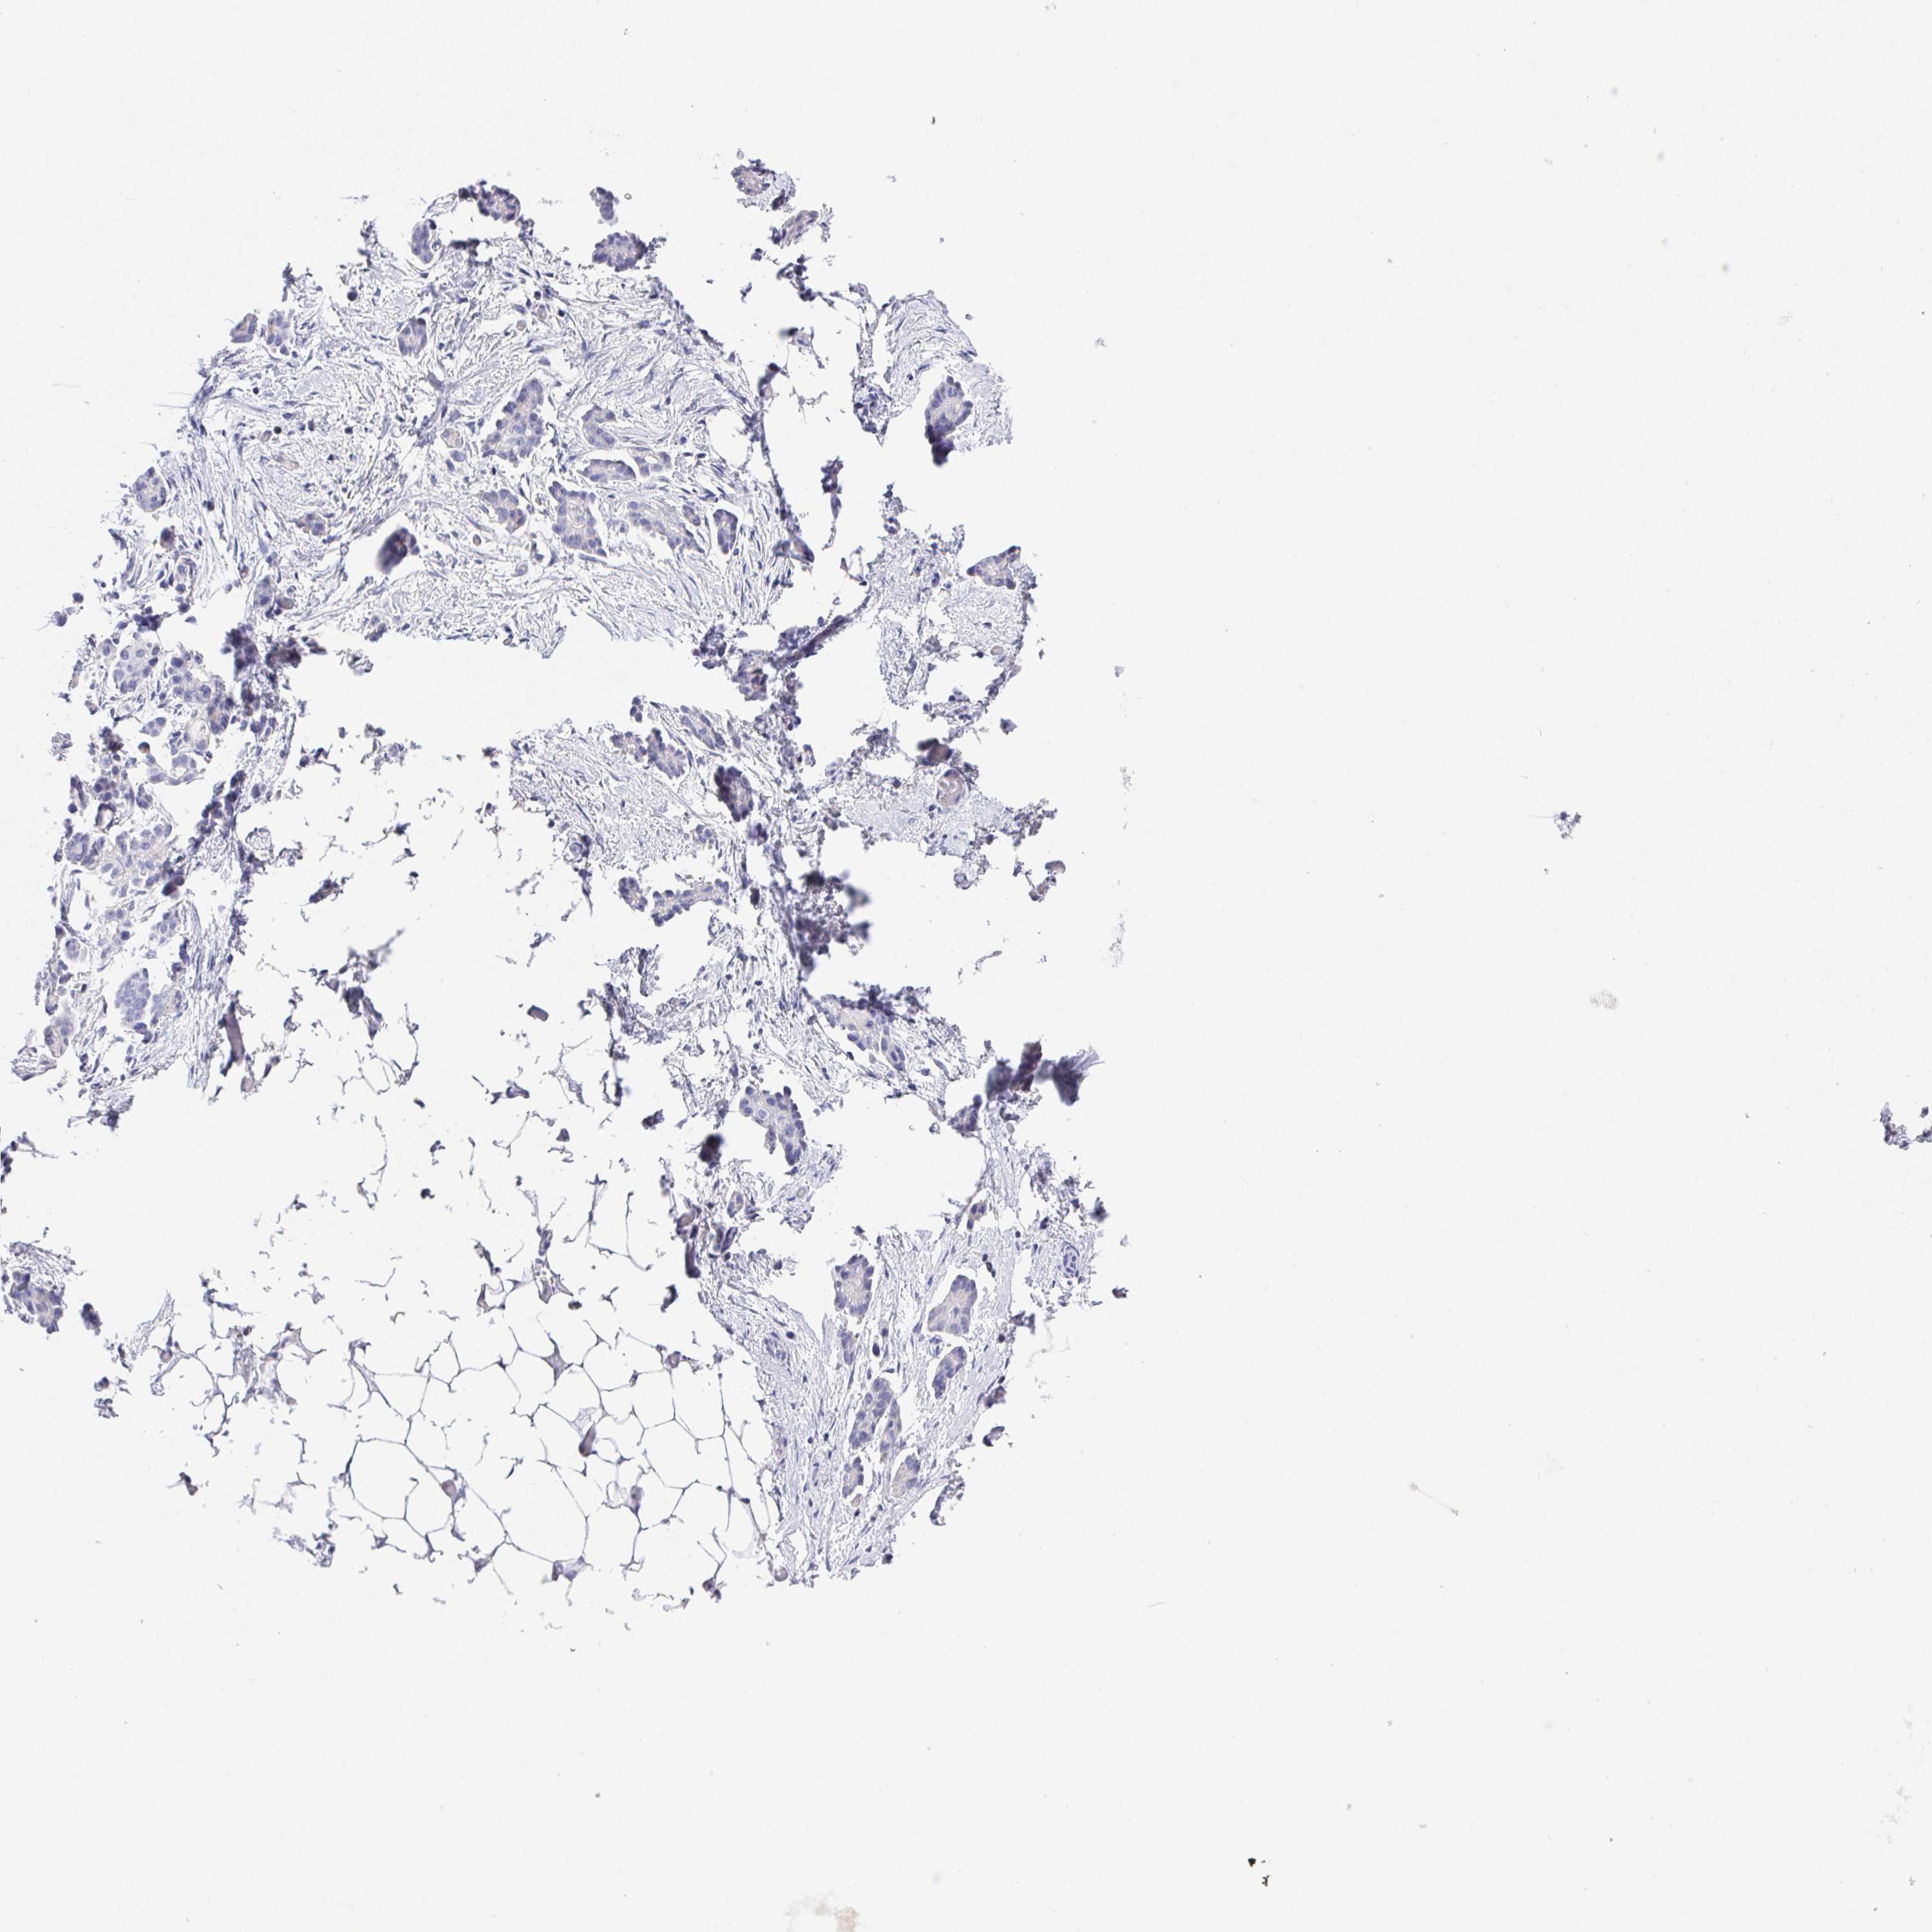

OVARIAN CANCER - Protein expressioni

A mouse-over function shows sample information and annotation data. Click on an image to view it in a full screen mode. Samples can be filtered based on level of antibody staining by selecting one or several of the following categories: high, medium, low and not detected. The assay and annotation is described here.

Note that samples used for immunohistochemistry by the Human Protein Atlas do not correspond to samples in the TCGA dataset.

Antibody stainingi

Antibody staining in the annotated cell types in the current human tissue is reported as not detected, low, medium, or high, based on conventional immunohistochemistry profiling in selected tissues. This score is based on the combination of the staining intensity and fraction of stained cells.

Each image is clickable and will lead to virtual microscopy that enables deeper exploration of all samples and also displays staining intensity scores, fraction scores and subcellular localization as well as patient and tissue information for each sample.

Antibody HPA064183

Staining

High

Medium

Low

Not detected

Intensity

Strong

Moderate

Weak

Negative

Quantity

>75%

75%-25%

<25%

None

Location

Nuclear

Cytoplasmic/membranous

Cytoplasmic/membranous,nuclear

Cystadenocarcinoma, serous, NOS

Cystadenocarcinoma, mucinous, NOS

Carcinoma, endometroid